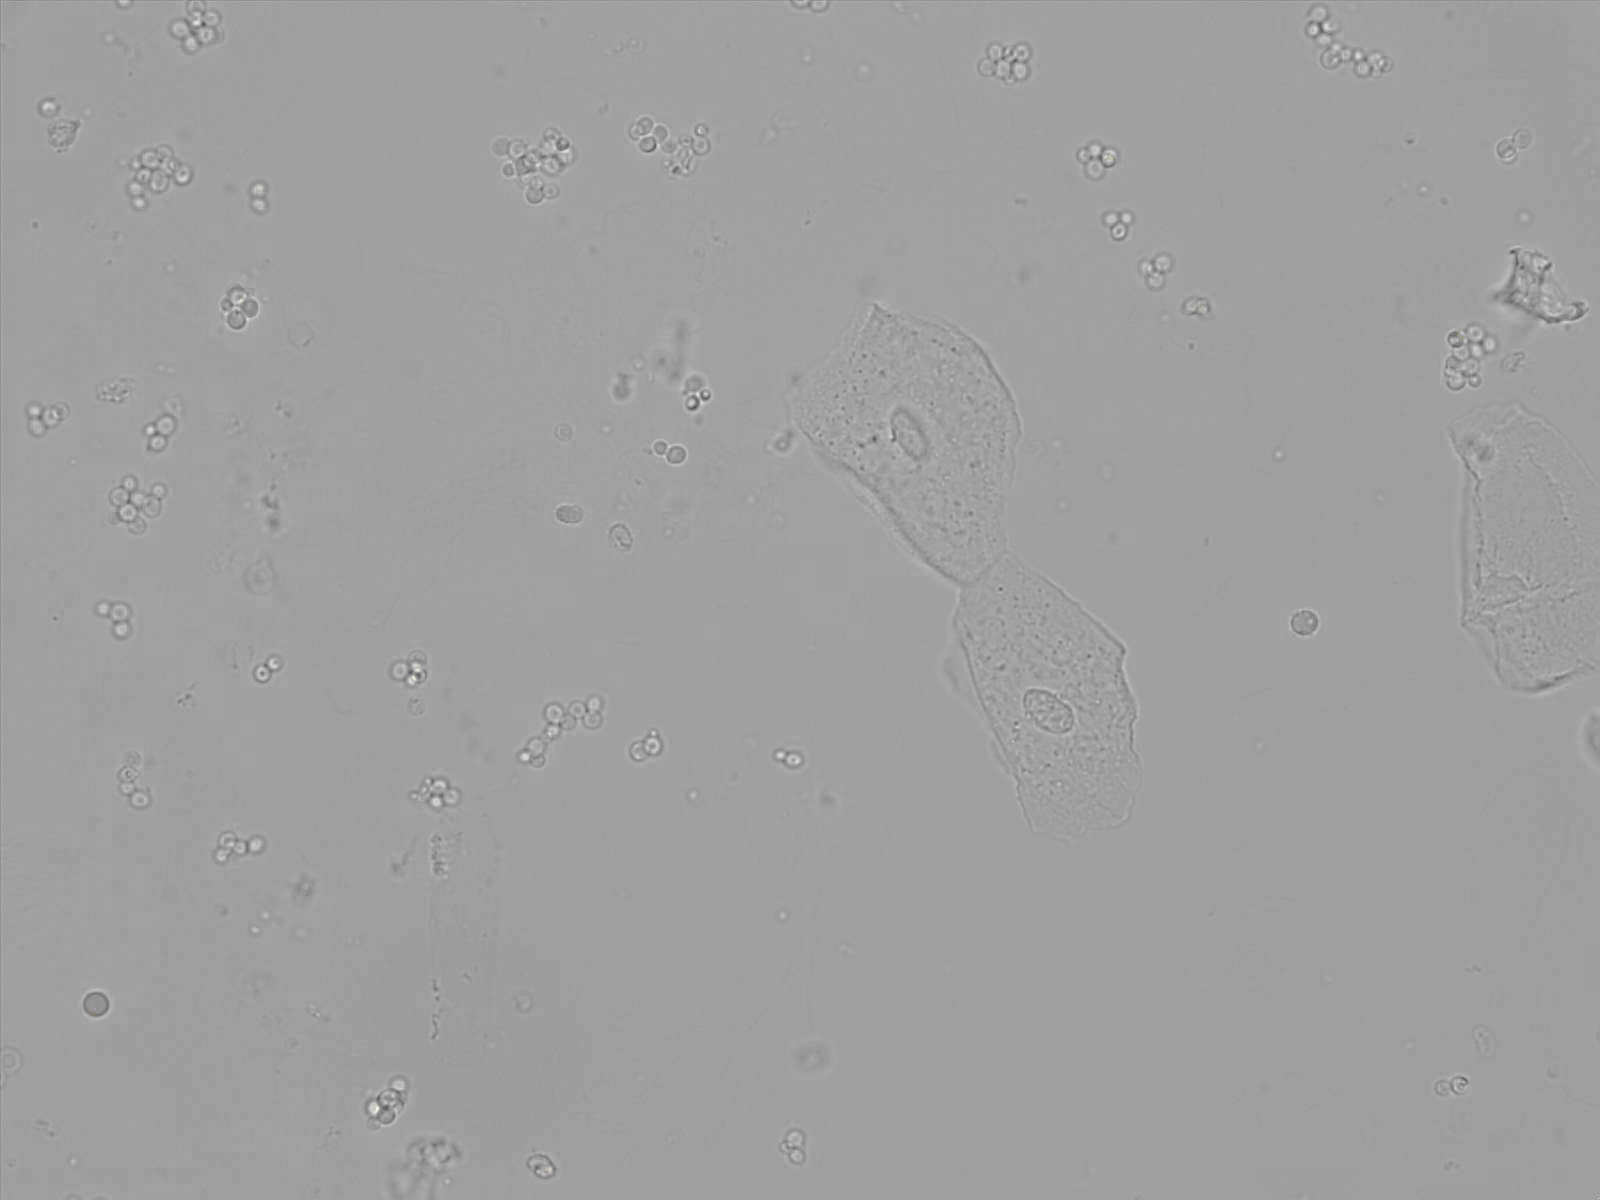

Yeast is a fungus often caused in humans by Candida Albicans. This yeast is normally present in small amounts in the body. However, overgrowth can occur when the balance between the yeast and healthy bacteria is disturbed, such as by antibiotics, a weakened immune system or diabetes.

Under the microscope, yeast is often recognized by its typical yeast straightening (roundish cells) and fungal threads (hyphae), which look like thin thread-like structures. Yeast cells may appear in clusters or chains, depending on the type of infection. Precise differentiation based on urine is often not possible.